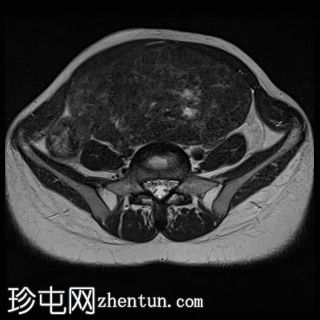

子宫后壁可见一个边界清晰、体积较大的浆膜下肌瘤,大小约为16.1 x 10.5 x 14.4 cm(宽 x 深 x 高)。

该肌瘤在T1加权像上呈中等信号,在T2加权像上呈低信号,内部区域呈囊性变性。

该肿块导致正常子宫结构严重变形。增强扫描显示轻度不均匀强化,未见弥散受限征象或提示恶性肿瘤的可疑强化。